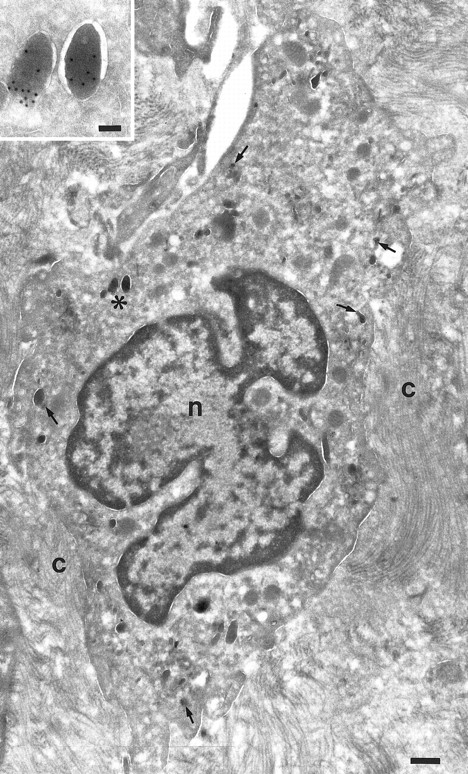

Fig. 4.

Localization of TGF-α in macrophages. Cryosection of a macrophage from a nasal polyp labeled for TGF-α. A few granules are labeled for TGF-α (arrows). Nucleus, (n); bundles of collagen (C). Inset is a higher magnification of the marked granules (asterisk) to show the gold labeling. Bars = 500 nm, inset = 100 nm.

In promonocytes from the bone marrow, as well as monocytes from bone marrow and peripheral blood, TGF-α was localized in abundant electron-dense granules (Figs 1 and 2). The pattern of granules was similar in bone marrow promonocytes (Fig 1) and mature monocytes (Fig 2). These cells can be distinguished by the presence of bundles of filaments in the cytoplasm and a rounded or oval nucleus in promonocytes. Indications for the release of TGF-α–positive granules came from monocytes incubated for 24 hours with IL-10 and IFN-γ and thereafter labeled with anti–TGF-α. At the ultrastructural level, these monocytes have an activated appearance (Fig 3): ruffles on the cell membrane on one side, the nucleus localized at the opposite side and less TGF-α–positive granules than in untreated cells. Moreover, the remaining TGF-α containing granules are located underneath the cell membrane, mainly under the ruffles. Macrophages in nasal polyps (Fig 4) contained very few TGF-α–positive granules.